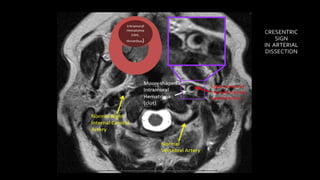

• #162 Here is an example of a young patient presenting with severe acute neck pain SHOWING left ICA dissection ON T2wi AS crescentric shaped hyperintense intramural hematoma causing expansion of the artery. However there is no narrowing of ICA lumen

• #163 Another example showing circumferential intramural hematoma seen bilaterally causing expansion of the bilateral ICA . There is narrowed lumen of the right ICA and open lumen of the left ICA